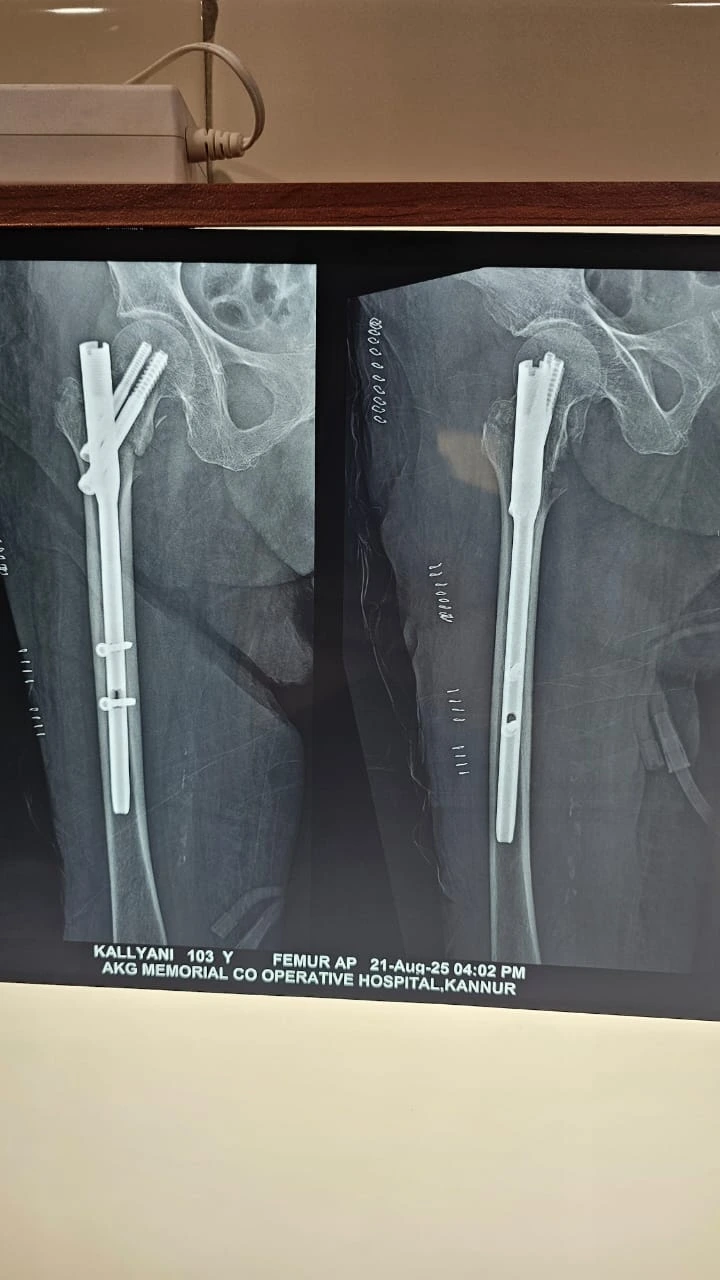

Image gallery